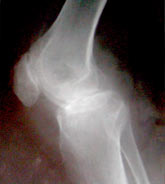

Koch's knee arthritis preop xray lat

Koch's knee arthritis preop